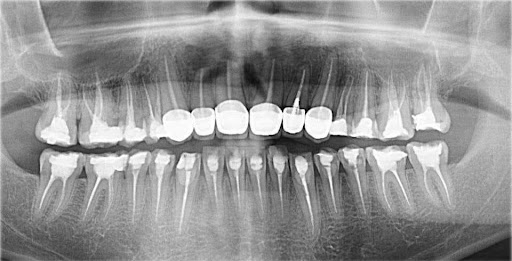

Trước khi bước vào thực hiện làm răng sứ, các bác sĩ tại Nha khoa HanSeoul sẽ tiến hành thăm khám tổng quát để xác định được tình trạng răng miệng của khách hàng. Sau đó tiến hành chụp hình cận răng và hướng dẫn khách hàng chụp phim X-quang CT để có hình ảnh trực quan nhất về cấu trúc răng – hàm. Từ đó xác định chính xác được mức độ tình trạng của răng cần khắc phục.

Trong trường hợp nếu bác sĩ phát hiện ra bệnh lý răng miệng, bệnh nhân cần điều trị triệt để rồi mới bắt đầu tiến hành bọc răng sứ,